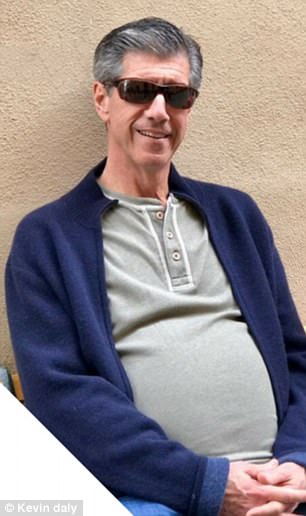

El hombre fue sometido a una tomografía computarizada en el Hospital Lenox Hill de la ciudad de Nueva York.

Los resultados fueron estremecedores, su vientre contenía “una masa extremadamente grande”, la cual se trataba de un tumor.

Sin embargo, esa masa resultó ser un raro tumor canceroso llamado liposarcoma, que crece en el tejido adiposo. Los cirujanos decidieron que el mejor tratamiento sería eliminarlo.

Al realizar las primeras incisiones, los médicos estimaron que el tumor debía pesar alrededor de unos 5,4 kilos. Pero durante la operación, pudieron notar que esa masa era más del doble del tamaño que calculaban y se había enrollado alrededor del riñón.

Los cirujanos estuvieron más de seis horas intentando eliminar el tumor, y finalmente, al removerlo por completo, puedieron ver que pesaba al rededor de 13,6 kilos.

El doctor Julio Teixeira, contó que fue el tumor más grande que extrajo en sus 30 años de práctica. Al describir cuánto pesaba esa masa, dijo: “una cosa es ver la imagen. Otra es tener este enorme tumor gigante en tus manos”.